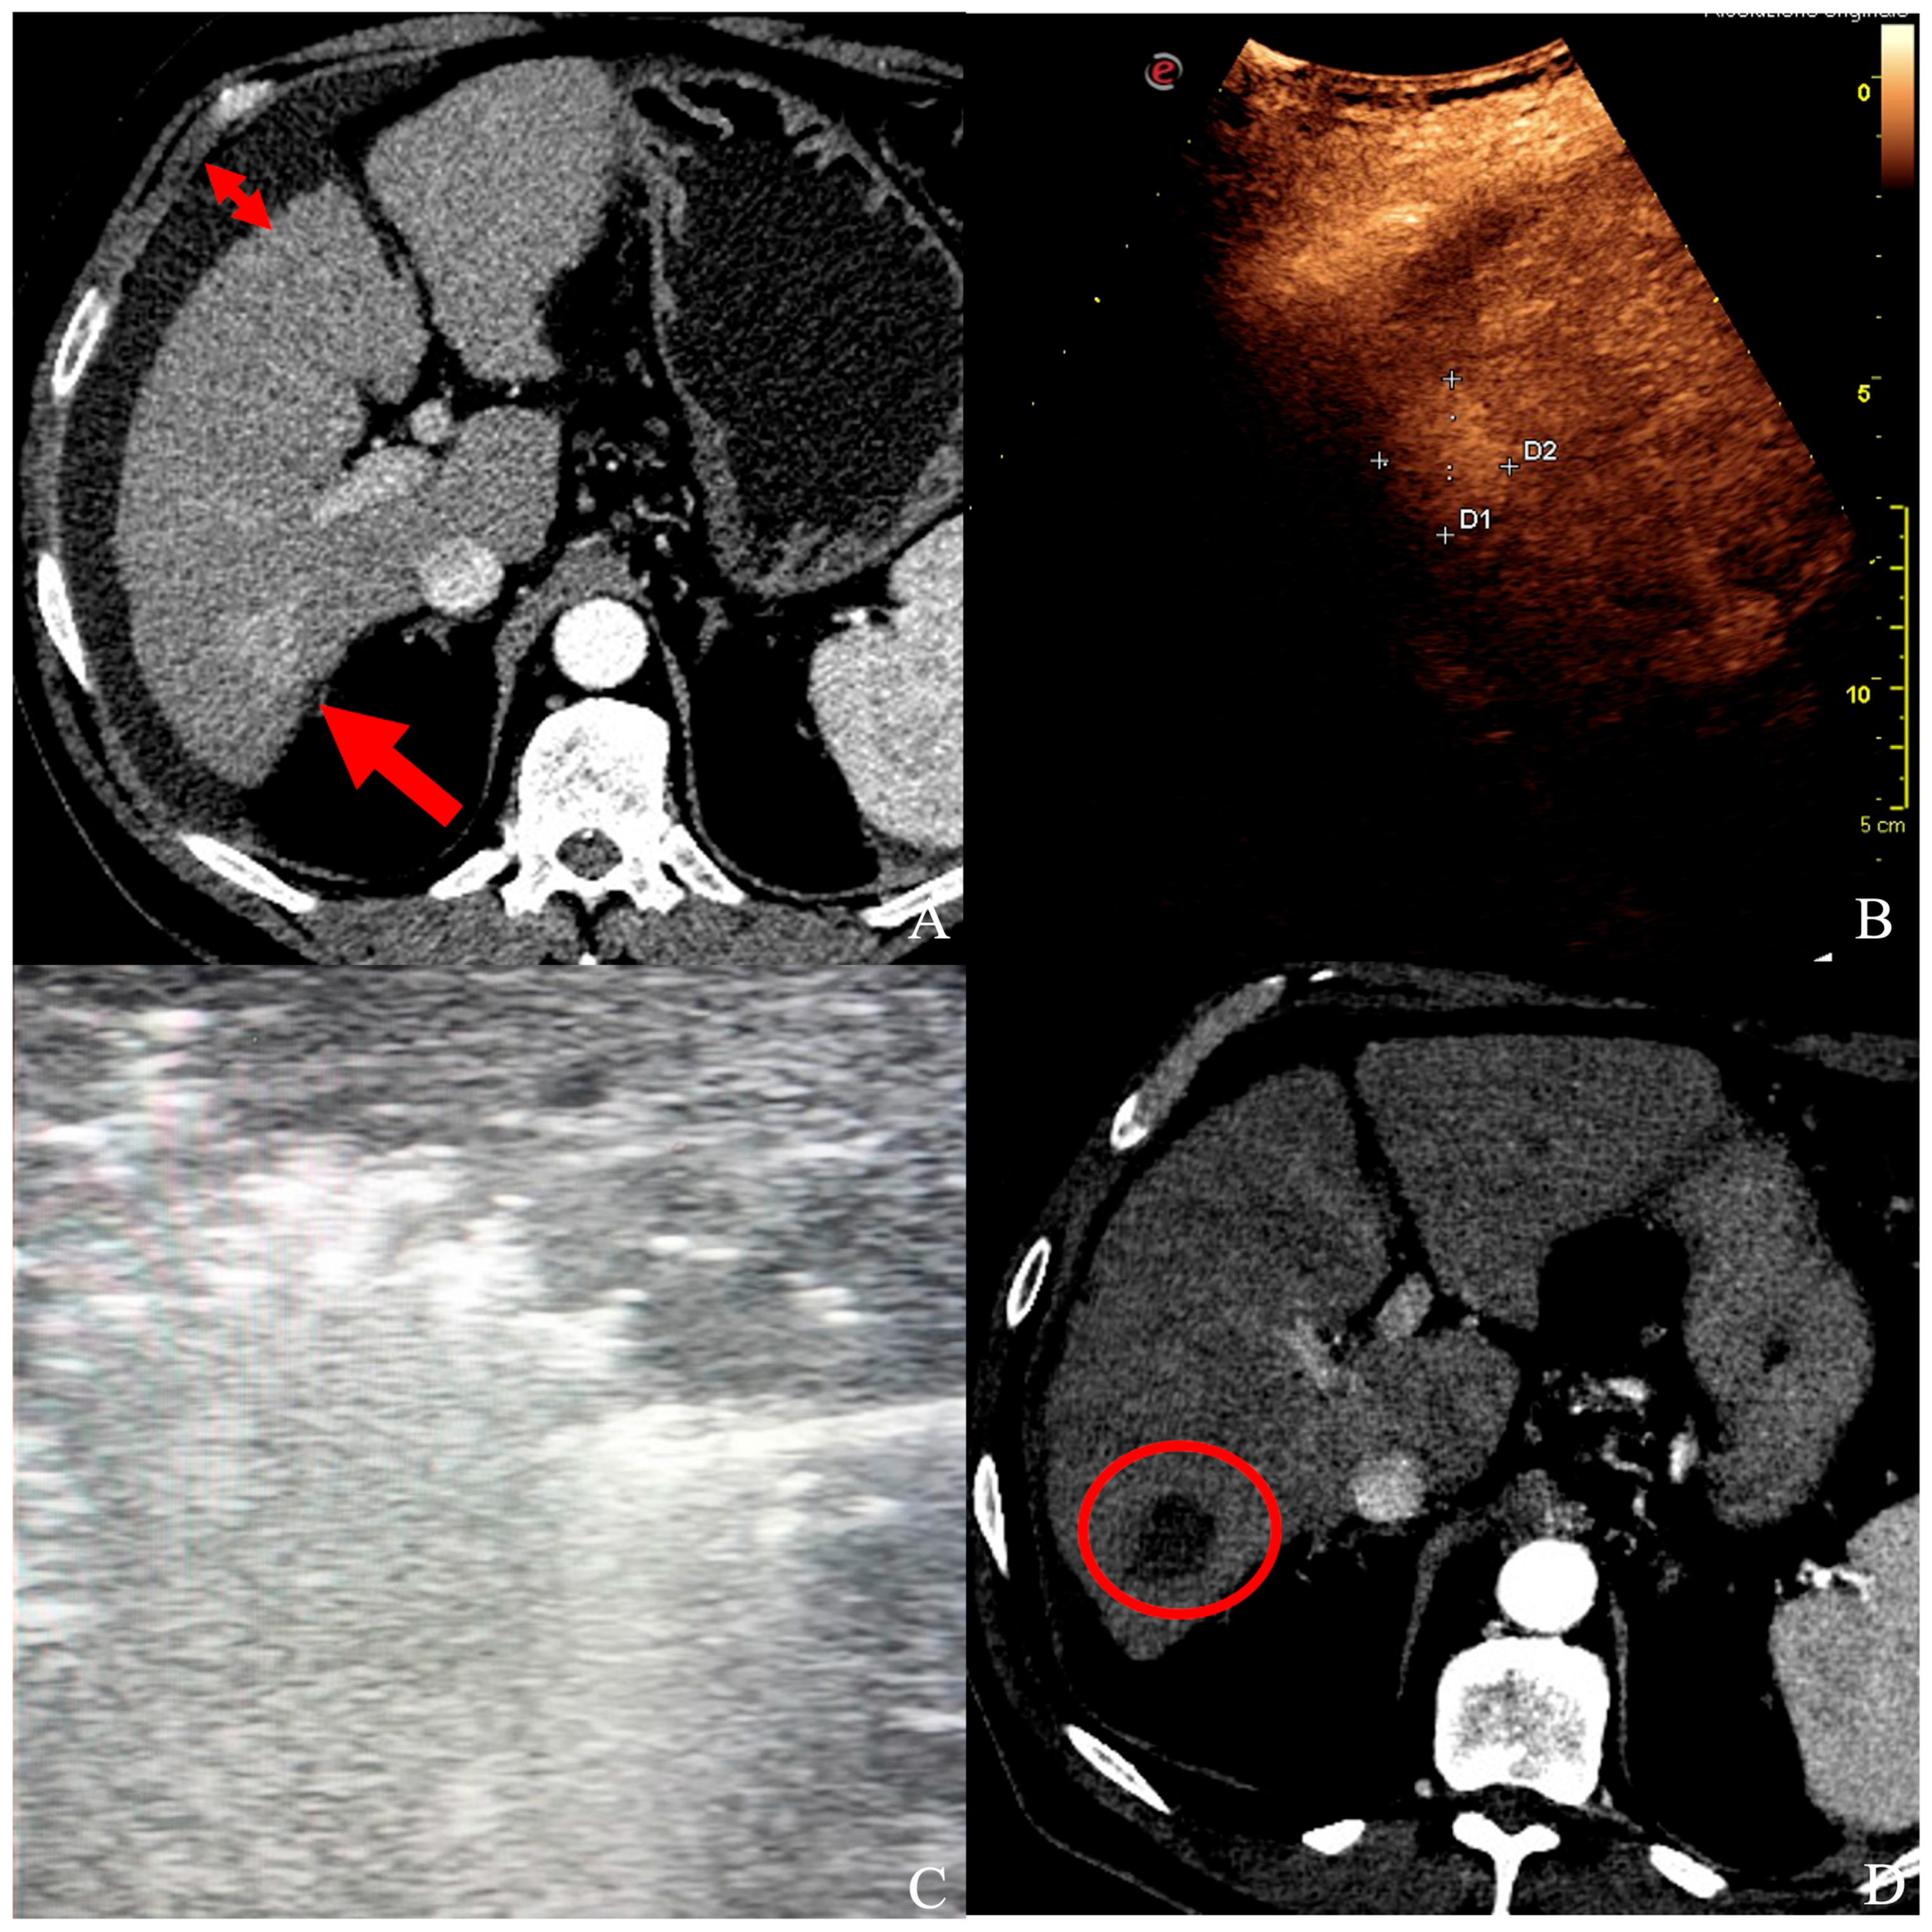

2.2. Laparoscopic and Laparotomic Ablation